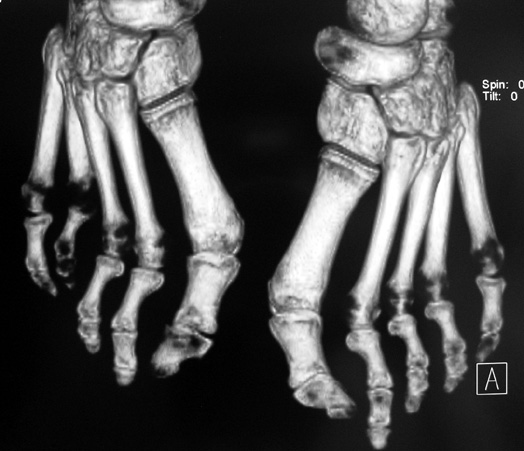

El parmağı (metakarp) ve ayak parmağı (metatars) kısalıkları doğuştan tek başına, geniş bir sendrom grubuyla birlikte, travma sonrası, Freiberg hastalığı (avasküler nekroz) sonrası görülebilir.

Doğuştan metakarp ve metatars kısalığının görülme sıklığı 1/1000’den azdır. Kadınlarda erkeklere göre 5 kat daha fazla görülür ve sıklıkla (%72) iki taraflıdır. En sık 4. parmak tutulur. Bu tür olgularda sorunun nedeni tam olarak bilinmemekle brlikte deformitenin genellikle epifiz plağının erken kapanmasından kaynaklandığı düşünülmektedir.